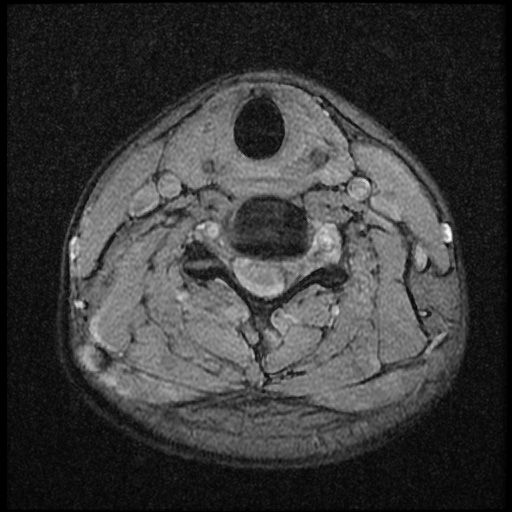

이 MRI 사진은 21년도 사고 당시 찍은 MRI 사진 입니다. 확인 부탁드립니다~

전체 mri를 다 봐여겠지만 보여주신 mri 컷에서는 의미있는 경추 디스크탈출이 보이지 않습니다.